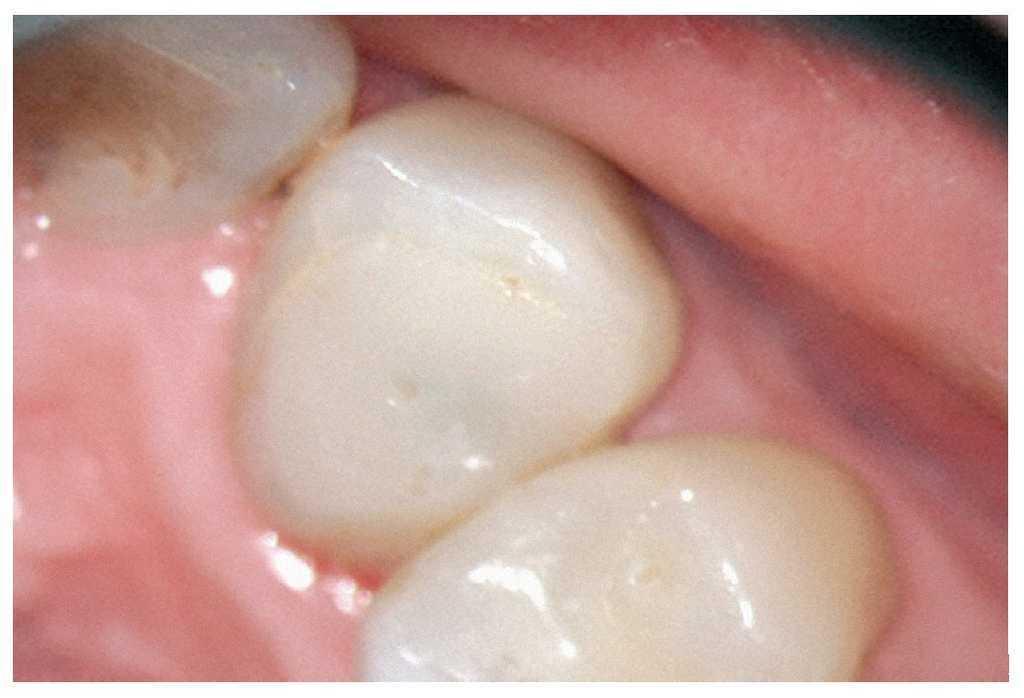

Entre las primeras fases del tratamiento endodóntico se encuentran la preparación de una cavidad de acceso primaria y de otra secundaria adecuadas y la localización y exposición de las entradas de los conductos radiculares.

Esta tarea puede ser complicada dependiendo sobre todo de la región del maxilar, del estado de la pulpa y del tipo de restauración existente. Cualquier concesión que se haga en esta fase puede influir negativamente en el desarrollo posterior del tratamiento endodóntico15 (fractura de instrumentos, perforación, imposibilidad de exponer y preparar los conductos). El uso de instrumentos ópticos de aumento y una buena iluminación del campo de trabajo no siempre son suficientes. Si se trabaja con un microscopio óptico habrá que preparar la cavidad de acceso con visión indirecta, a través de un espejo, y muchas veces el contraángulo obstaculiza la visión directa sobre la cavidad de acceso22,39,44. En comparación con las fresas convencionales que se fijan al contraángulo, el uso de puntas ultrasónicas especiales mejora notablemente la visión de la zona en la que se ha de eliminar dentina o material de restauración (figs. 1a a 1d).

Figura 1a. Un cálculo pulpar obstruye la entrada del conducto radicular palatino del diente 16.